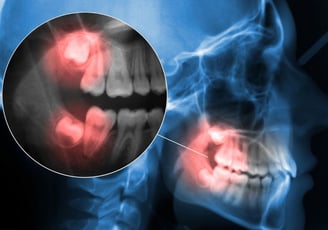

Cirurgias de sisos, implantes dentários, biopsias, diagnósticos de patologias orais